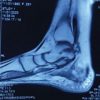

MRI scan of the right hip demonstrated an osteochondral defect of the femoral head with associated subchondral edema (Fig. 3a and b). There were no obvious signs of avascular necrosis (AVN) of the femoral head.

Figure 3: (a and b) Magnetic resonance images showing altered signal intensity in the anterosuperior aspect of the right femoral head.